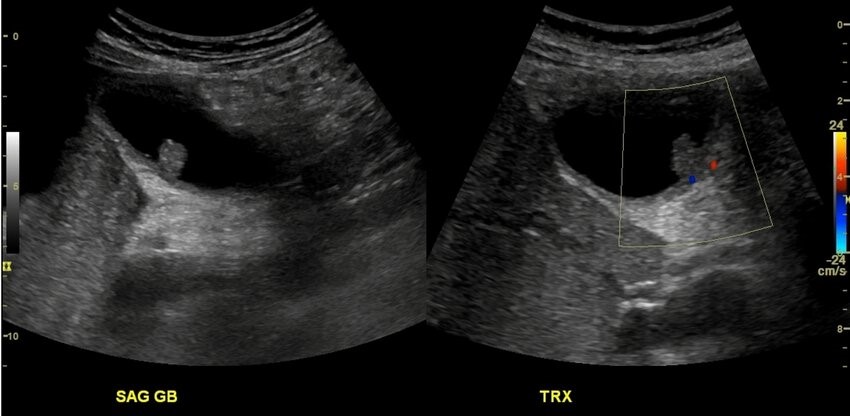

При трансабдоминальном УЗИ билиарной системы выявлено:

Ультразвуковое заключение:

Эхографические признаки полипоидного образования желчного пузыря 11 мм на широком основании. С учетом размера и факторов риска — находка подозрительна; рекомендована консультация хирурга (вопрос холецистэктомии) / дообследование (EUS/CEUS по доступности).

Допплер

Нет/минимальная

Умеренная

Выраженная, хаотичная